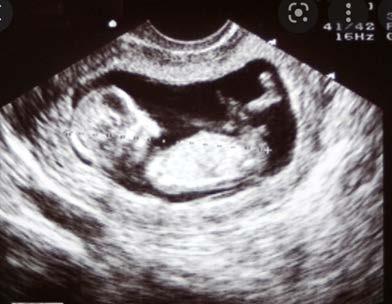

Ultrasound picture of 8 week old embryo

The ultrasound images below show the difference in the first trimester and the second trimester.

The image below shows how an ultrasound is used to monitor a baby’s development and look for abnormalities.

First trimester ultrasound Second trimester ultrasound